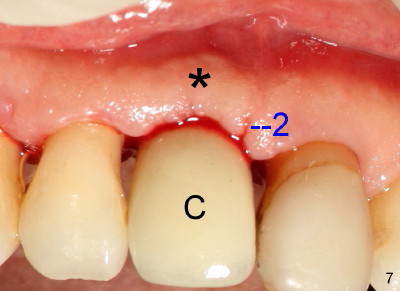

Fig.4-7 show modified semilunar incision helps form cosmetically-pleasing attached gingiva. Prior to uncover, the buccal plate of #8 (*) is concave, as compared to those of the neighboring teeth. The main incision is indicated by black line, lingual to the crest so that the buccal flap is more bulky. It is curved and festooned to create the future cosmetic buccal gingival margin. If the main incision is placed too lingual to expose the implant, one or two accessory incisions (red) can be made. After insertion of 4x6.5 mm non-shouldered abutment 3 mm post, PVS impression is taken. Fig.5 shows temporary crown in place (T) with two vertical mattress suture in the mesial and distal papillae. Two accessory incisions are approximated. The attached gingiva over the temporary crown immediately becomes bulky (*). Two weeks later, the temporary crown is removed. The accessory incision #1 has healed, while #2 is healing (Fig.6). The temporary crown helps form a nice socket around the abutment (A). The buccal attached gingiva (*) is leveling with that of the neighboring teeth, as compared to concavity before uncover (Fig.4). Fig.7 shows the gingiva around the crown (to be cemented) with healing incision #2. The buccal attached gingiva(*) is as bulky as immediately after uncover (Fig.5). Return to original article